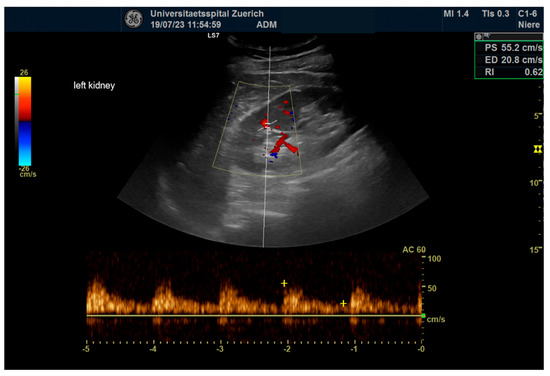

2.4. Ultrasonography

3.6. Ultrasound Evaluation

3.7. Renal Functional Outcomes

| Renal Parameters (n = 64) | Pre-Operative | Post-Operative | p |

|---|---|---|---|

| RRI | 0.66 ± 0.06 | 0.67 ± 0.07 | ns |

| Length (mm) | 107.1± 13.8 | 107.9 ± 14.5 | ns |

| Wide (mm) | 52.4± 7.9 | 52.9 ± 7.8 | ns |

| Parenchymal margin (mm) | 18.3 ± 3.2 | 18.6 ± 2.8 | ns |

| Laboratory Results (n = 32) | |||

| Creatinine (µmol/L) | 92.1 ± 18.5 | 90.0 ± 28.2 | ns |

| eGFR (ml/min) | 68.8 ± 15.8 | 72.3 ± 18.0 | ns |